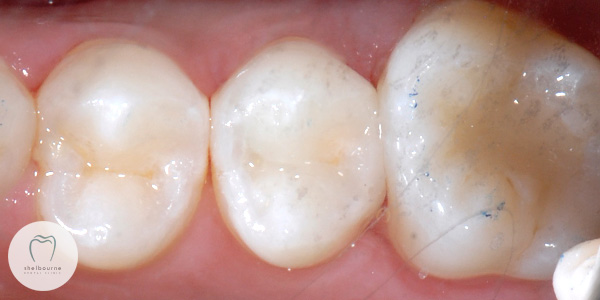

Now I have the decay removed and the cavity is nice and clean, I can go ahead and restore the tooth. We’re going to use tooth coloured filling material (composite resin) to restore the tooth to normal.

After removing the green rubber dam, I do a quick check of the bite to make sure it feels comfortable for the patient. I also make sure my filling is nice and snug against the neighbouring tooth. It should be “nice and tight” when you floss it. If it isn’t, then food is going to get stuck in here again and cause further decay 🙁

And that’s it folks. Here is the final image of the filling in the tooth. I just hope that my patient will be a champion at flossing between her teeth from now on 😉